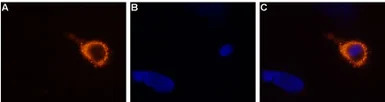

Live cell imaging analysis of living rat dorsal root ganglion (DRG) using GTX54763 TRPV3 antibody.

Panel A : Primary antibody (Orange)

Panel B : Hoechst 33342 for nuclear staining (blue)

Panel C : Merged images of Panel A and B

Dilution : 1:50-1:100